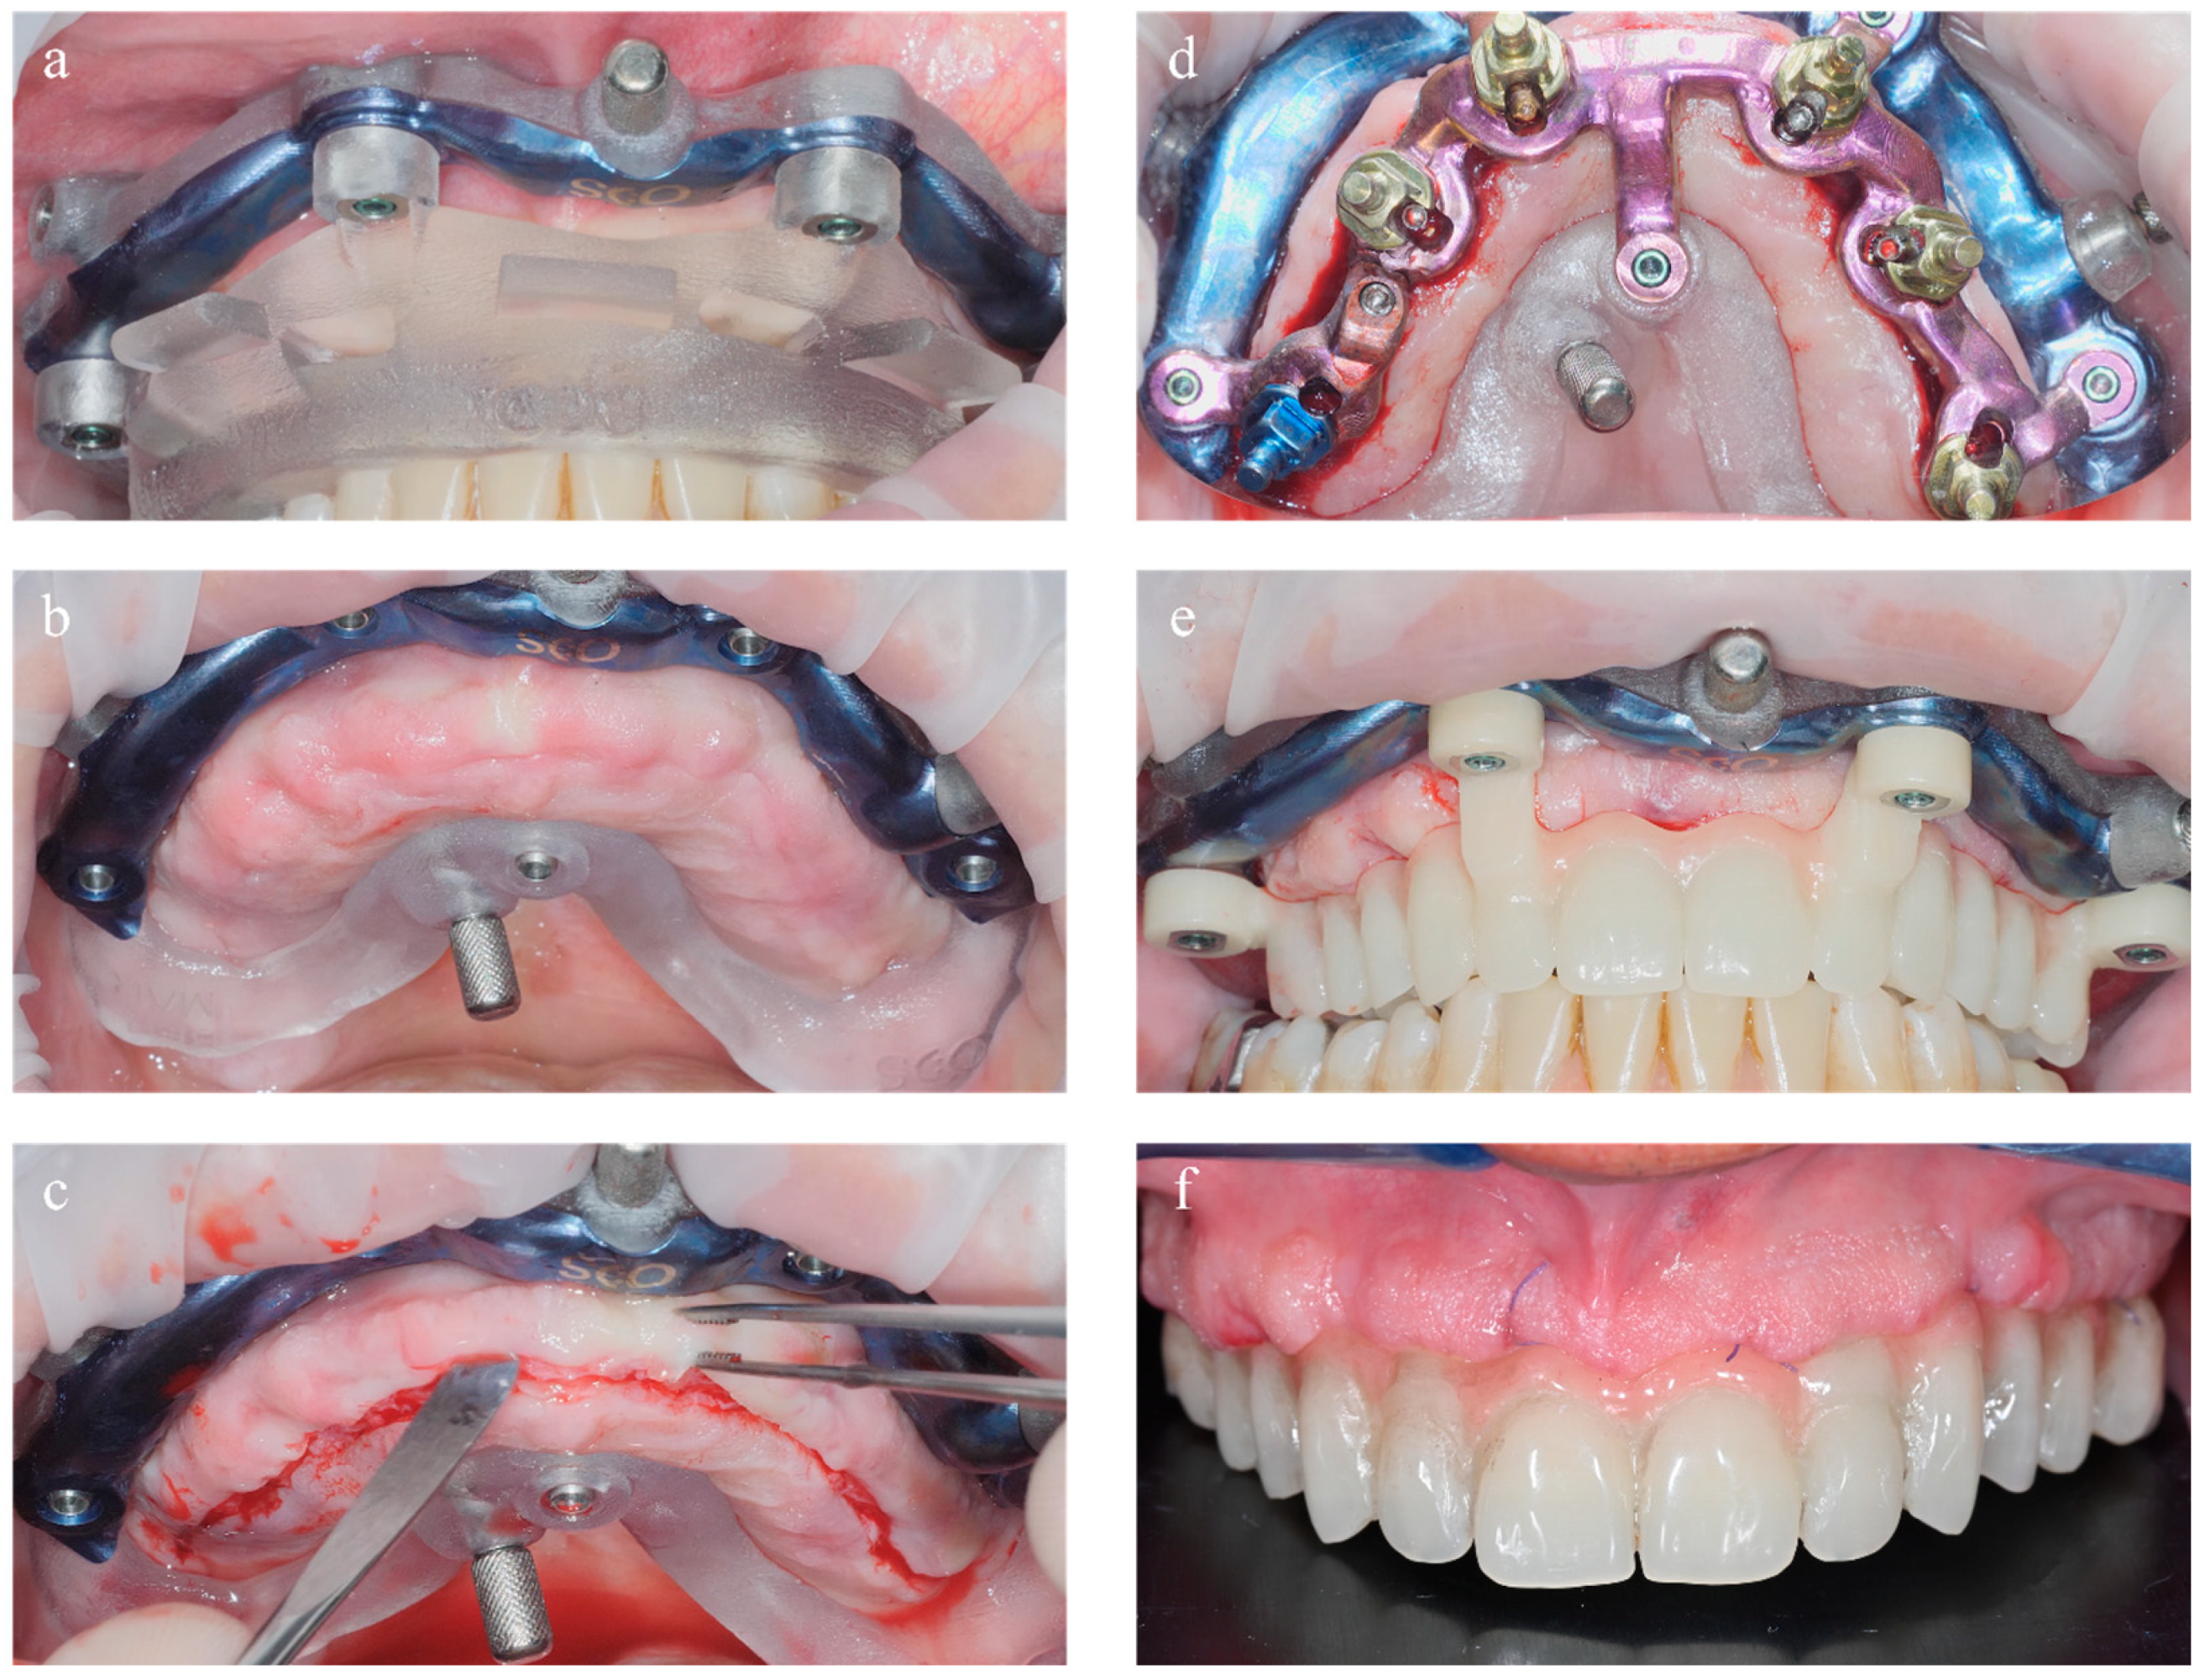

2.2. Surgery

2.3. Prosthetic Restoration